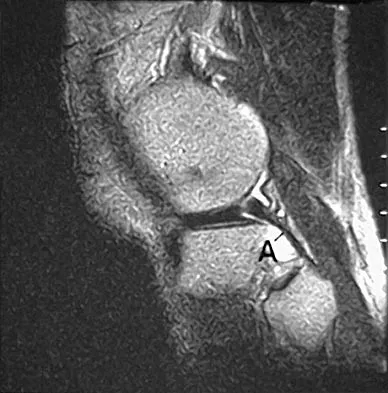

The primary function of structure "A" in Figure 29 is to limit

Explanation